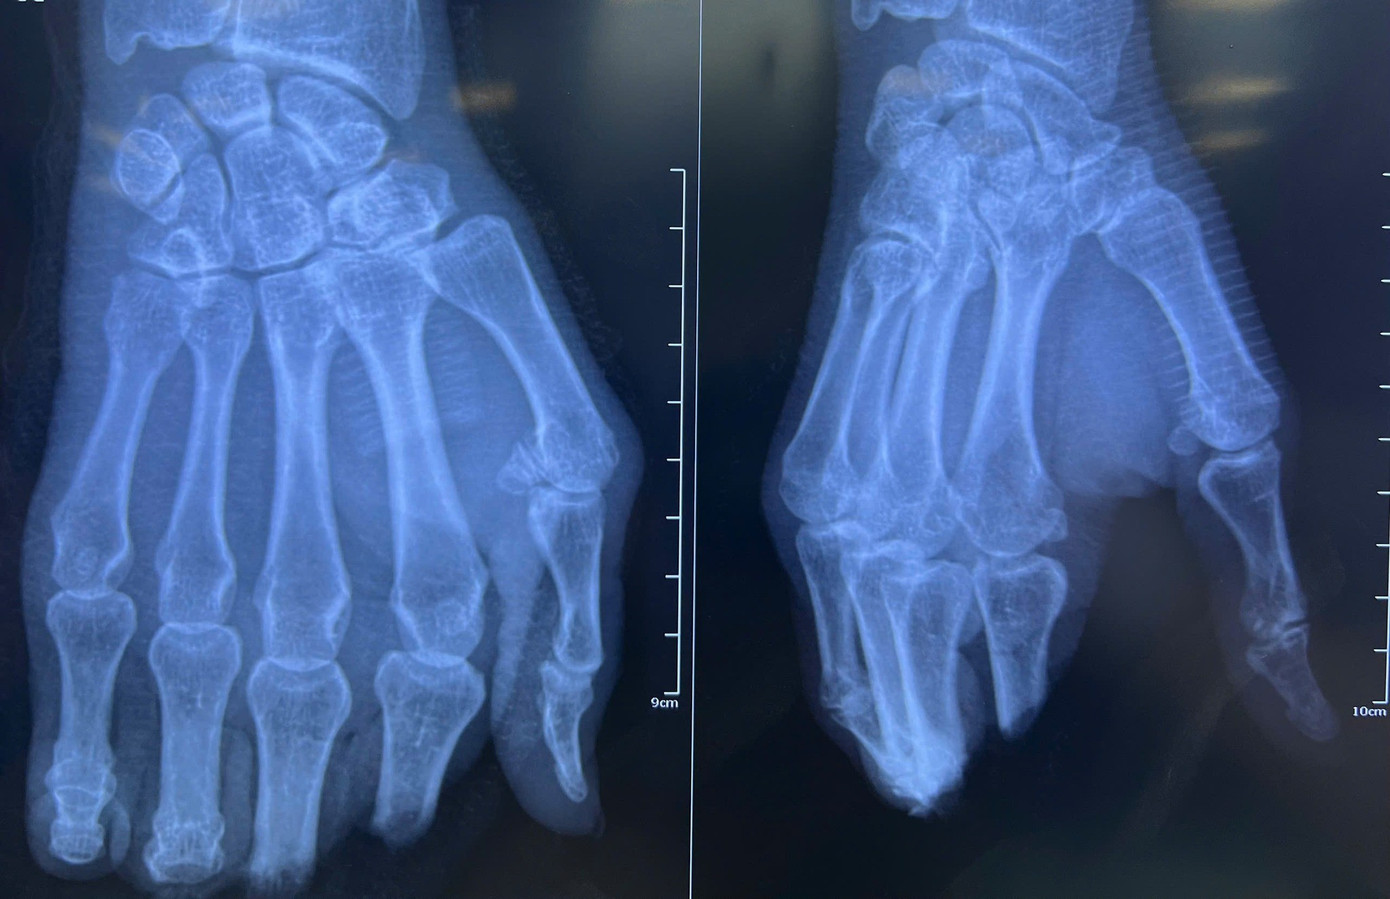

Theo bệnh sử, ông Q. nhập viện vào chiều 16/3 trong tình trạng đứt rời các ngón II, III, IV, V của bàn tay phải. Qua thăm khám, các bác sĩ nhận định đây là ca chấn thương phức tạp khi vị trí đứt nằm tại khớp liên đốt gần và đốt xa, kèm theo tình trạng dập nát mô mềm nghiêm trọng. Bên cạnh đó, bệnh nhân lớn tuổi và có tiền sử hút thuốc lá lâu năm, làm tăng nguy cơ tắc mạch sau khi nối.

4 ngón tay của người bệnh bị đứt lìa sau tai nạn nghiêm trọng

BS-CKII Nguyễn Cao Viễn – Phó trưởng khoa Ngoại chấn thương - Chỉnh hình, Trưởng đơn vị Vi phẫu - Tạo hình của bệnh viện cho biết, ê kíp đã tiến hành ca phẫu thuật vi phẫu kéo dài suốt 8 giờ liên tục, từ 18h ngày 16/3 đến 2h sáng ngày 17/3. Các bác sĩ thực hiện đồng thời nhiều kỹ thuật rất khó như cố định xương, nối mạch máu, thần kinh và khâu nối gân gấp – duỗi cho từng ngón tay.

“Quá trình phẫu thuật gặp không ít khó khăn do mạch máu ở đầu xa rất nhỏ và bị bầm dập nhiều, đòi hỏi thao tác cực kỳ chính xác và tỉ mỉ để bảo tồn mạch máu và đảm bảo việc nối thành công. Sau phẫu thuật các ngón tay của bệnh nhân đã hồng hào, lưu thông máu tốt. Dự kiến người bệnh sẽ tiếp tục được theo dõi và tập vật lý trị liệu để sớm phục hồi chức năng vận động” – BS Viễn nói.

Nỗ lực của các bác sĩ đã giúp người bệnh giữ lại 4 ngón tay